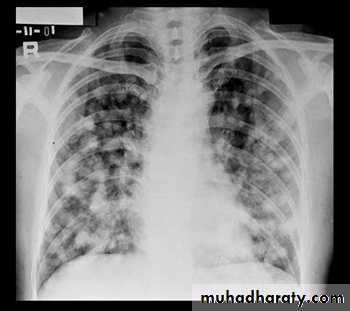

Miliary Tuberculosis. A cone-down view of a frontal radiograph demonstrates innumerable micronodular opacities characteristic of micronodular (miliary)

interstitial disease.

Transbronchial biopsy demonstrated caseating granulomas containing acid-fast bacilli.

Miliary TB

a frontal radiograph demonstrates innumerable micronodular opacities characteristic of micronodular (miliary) interstitial disease. Transbronchial biopsy demonstrated caseating granulomas containing acid-fast bacilli.